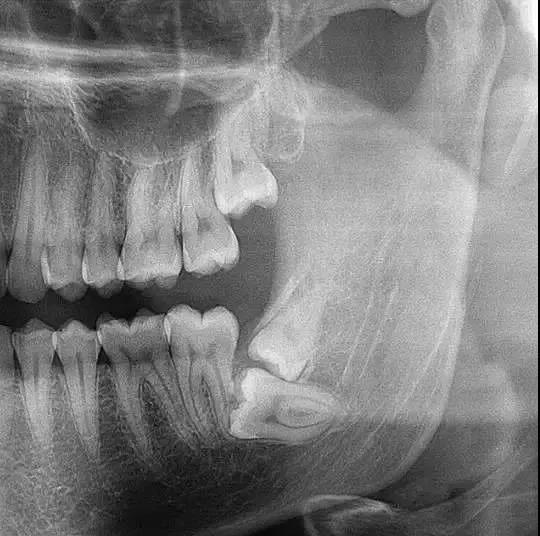

全景片就是可以在一张胶片上可以完整、清晰地显示上颌骨、下颌骨全貌,上下颌牙列情况,牙槽骨情况,能清晰显示上颌窦腔、窦壁、窦底情况,以及颞颌关节情况,并对颌骨周围疾病的诊断提供帮助。

因为全景片可以精确测定牙齿倾斜角度、牙周软组织情况、牙根情况、牙槽骨质情况,解剖形态的精确测量为医生术前的诊断分析与设计提供全景样图像依据,口腔医生借此能更好地为患者设计治疗方案。

拍摄全景片是口腔治疗之前很重要的一个检查过程,医生通过全景片可以观察到牙齿的健康状况,是否有隐形龋齿、埋伏阻生牙、多生牙、牙槽骨吸收、牙龈萎缩、口腔内是否长有瘤体等。在做牙齿种植、牙齿矫正、牙齿修复、智齿拔除等之前,均需要拍摄口腔全景片。